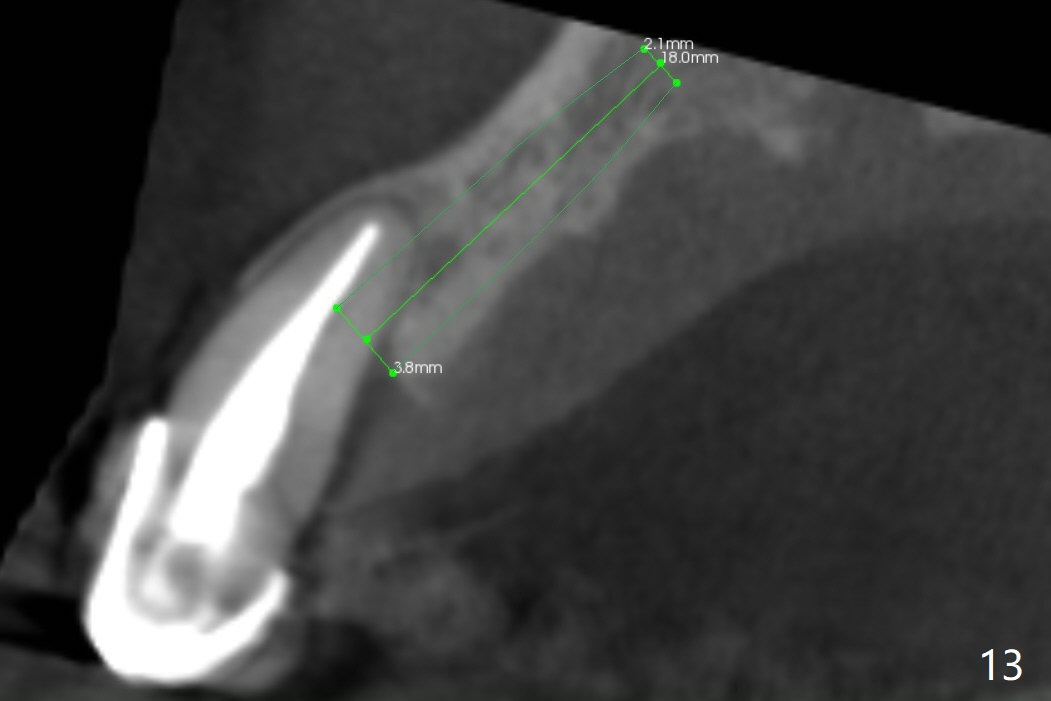

The tooth #10 has severe gingival recession (Fig.1) with loss of the buccal plate (Fig.2 *). After the initial osteotomy depth (Fig.3) increases by 2 mm, a 2.5x14(2) mm 1-piece implant is placed with insertion torque >60 Ncm (Fig.4). Palpation indicates the native bone apparently wider than CT shows. There is no sign of buccal or palatal plate perforation by palpation during osteotomy or implant placement. Vera Graft is placed repeatedly around the coronal threads (Fig.5-7 *). An immediate provisional is fabricated to close the socket (Fig.8). The buccal plate appears to collapse 1 month postop (cortical plate graft apparently more appropriate in this case); the margin of the provisional is trimmed so that the gingiva may grow incisally (Fig.9). The provisional dislodges several times postop due to short abutment. By nearly 4 months postop, the coronal bony defect seems to have been repaired (Fig.10 *). The tooth #11 has tenderness with bone loss (Fig.10 ^), corroborated by CT (distal bone loss, Fig.11 *). Since the apical bone is narrow (Fig.12), a narrow long implant is expected (Fig.13). Use an implant (3.5x13 mm) consistent with those at #14 and 15.